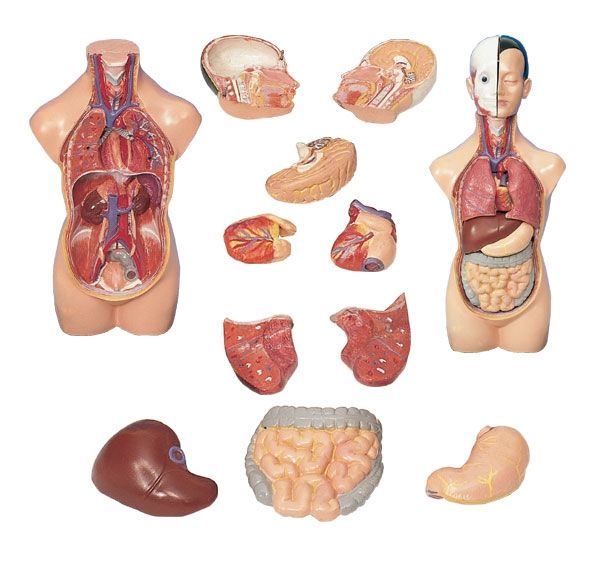

Изображения и визуализация внутренних органов человека

Раздел: Секреты мастерства